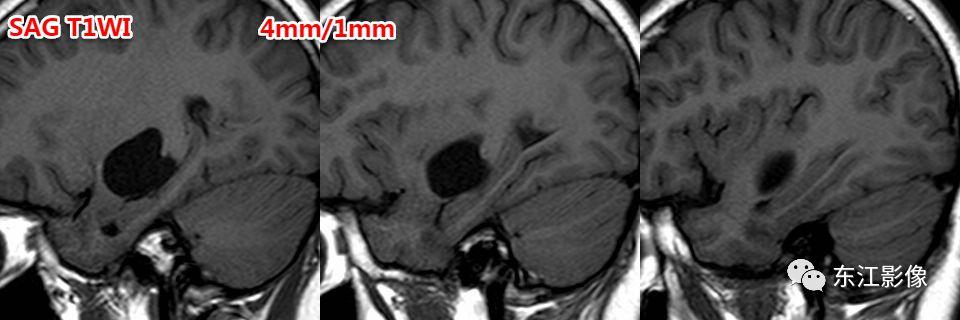

前穿质区扩大的血管周围间隙经常被误诊为脉络膜裂囊肿、腔隙性梗死灶。

信号上血管周围间隙与脉络膜裂囊肿没什么差异,形态学有一定的价值。

前穿质区是血管周围间隙最常见的部位,主体位于脑实质,层面合适时可见尖角(==》多方位观察)。

矢状或冠状薄层图像更容易显示向下突出的“残留”的脑实质!这是区分两者的重要影像证据!

脉络膜裂囊肿位于脉络膜裂,先引起脉络膜裂增宽,海马受压;压力大时,才向上压迫前穿质区脑实质。

注意,海马的压力较前穿质区脑实质小得多,所以脉络膜裂囊肿更容易压迫海马,因此主体部位不应是位于前穿质区!

注意,3D TOF MRA有断层图像,也是薄层的3D 梯度回波T1W图像,尽管对比度较差,但有时候是可以提供帮助的!